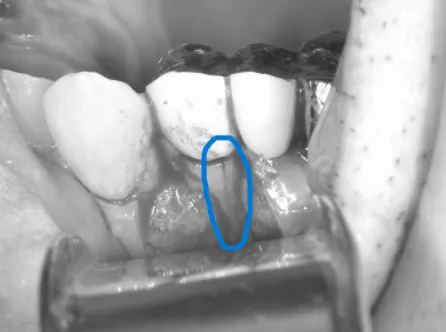

拡大図

マーカー部に亀裂

拡大してみると、歯を支えている骨が溶けている部分に一致した歯の亀裂があります。

ここの亀裂に細菌が侵入し、周りに炎症が起こることで骨が吸収し歯茎が腫れてしまっています。

この亀裂はCT撮影では写ってこない亀裂であったため、初めは根尖性歯周炎による歯茎の腫れと診断され歯根端切除を行う予定でした。

しかし、亀裂が手術時に発見され、今回のように縦断破折を認めてしまうと治療方針は大きく変わり抜歯が治療の最善策になります。